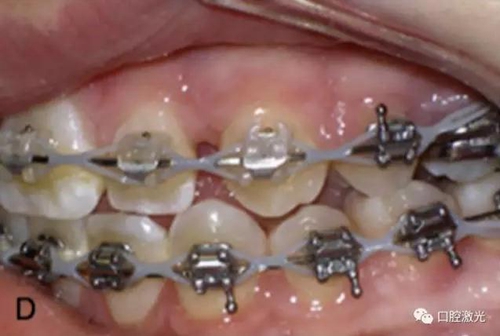

6周后效果

3周后效果